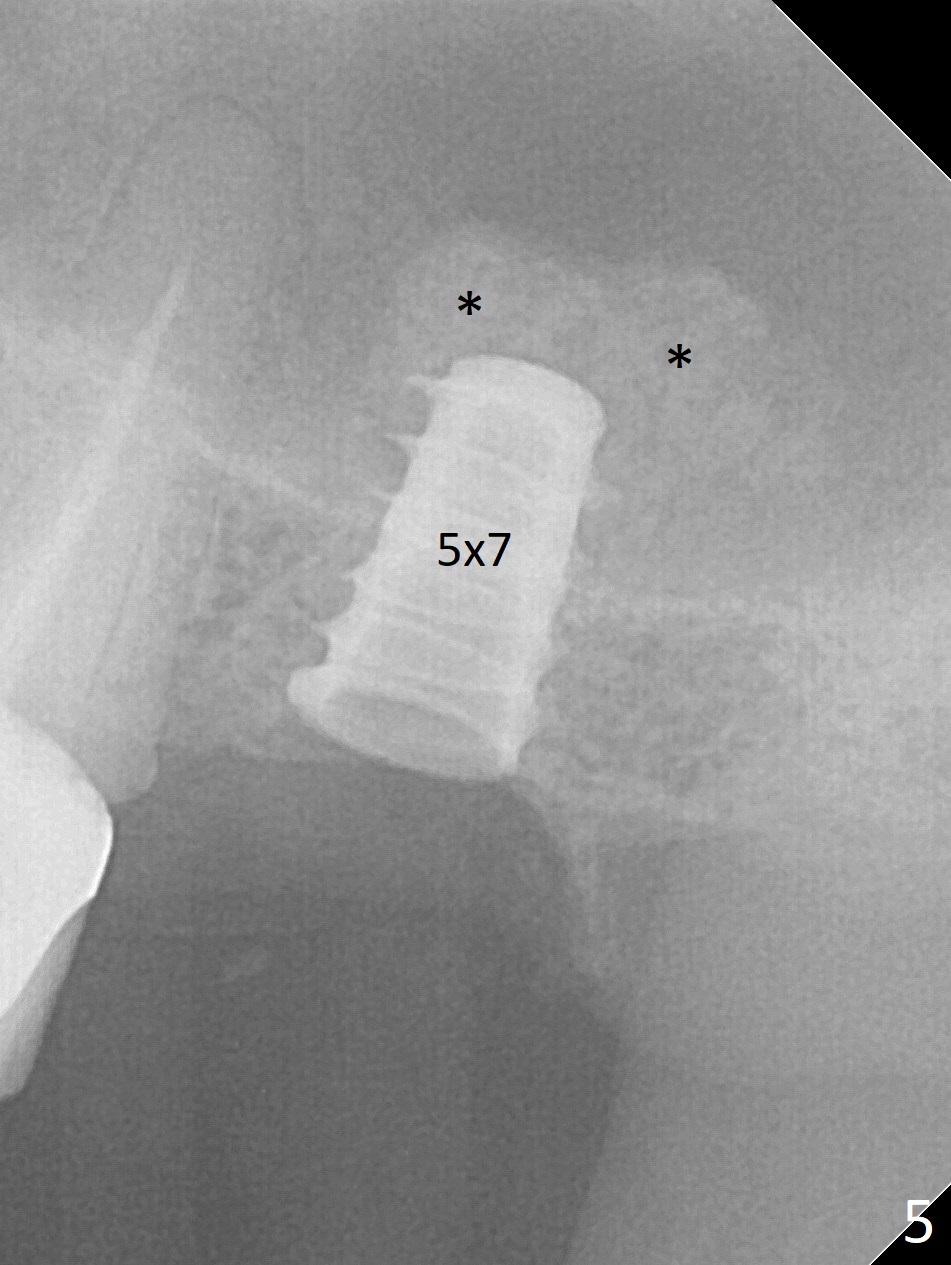

After removal of the mesial (M) and distal (D) residual roots of the tooth #15 (Fig.1,2), Magic Split is used to test bone density (high), followed by Magic Drills from Magic Sinus Lift Kit (for 4 mm) and Magic Surgical Kit (for 5 mm). It appears that the sinus floor has been perforated with the intact sinus membrane. Following minimal use of Magic Lifter, Vanilla Graft is inserted (Fig.3,4 *) and a 4x9 mm dummy implant is placed. After placement of more allograft (Fig.5 *), a 5x7 mm implant is placed with ~ 35 Ncm. With placement of a 5.5x4(2) mm abutment, an immediate provisional is fabricated to close the socket. Six months postop, the bone graft remains in the sinus around the apical end of the implant (Fig.6 *), while there seems no bone loss coronally (Fig.7). In fact there is, as shown later (Fig.8-11 < and lingual (L)). The crown is recemented 6 months post cementation (due to short abutment). The abutment seems to be incompletely seated. When the crown at #14 is reprep following #13 implant, the abutment screw is being untightened, the crown dislodges first. The abutment is confirmed short with more than enough occlusal clearance. After use of 5.5 and 6.0 mm bone profile drills, a 5x4(3) mm abutment is placed with complete seating.